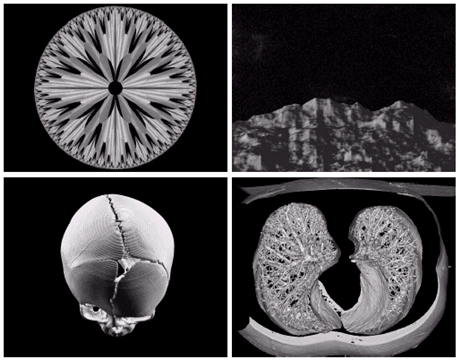

Gamma ray image

• 감마선의 투과성을 이용

• 주요 응용분야: 핵의학, 천문관측

Image

a) 환자에게 감마선을 방사하는 방사선 동위원소를 주사, 감마 검출기로써 영상을 획득 - 병소의 위치 파악에 유용 b) PET(positron emission tomography) image c) 백조자리 15,000년전의 가스성운의 감마선 영상 d) 핵반응 밸브로부터 나오는 감마선(밝은 부분)

X-ray image

• X선의 투과성을 이용

Ultraviolet image

• 주요 응용분야: 석판인쇄, 산업용 검사, 형광 현미경, 레이저, 생물학 영상, 천문 관측 등

a) 보통옥수수 b) 깜부기병에 걸린 옥수수 c) 백조자리 성운

• 전자현미경: SEM(scanning electron microscope)

• 전자빔을 쏘아 각 위치에서 빔과 샘플과의 상호작용을 기록

텅스텐필라멘트의 250x SEM영상, 손상된 IC의 250x SEM영상